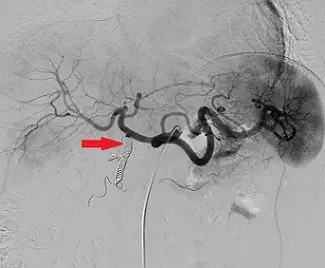

附圖為肝臟血管攝影,圖中紅色箭號所指血管主要經過何種栓塞治療?

圖片為一張**腹腔動脈血管攝影(celiac angiography)**的數位減影血管造影(digital subtraction angiography, DSA)影像,呈現黑白高對比的血管顯影畫面。

- 紅色箭號所指(影像中央):可見一段血管內呈現金屬線圈狀的高密度不透明影(metallic coils),呈鋸齒狀或彈簧狀排列,此即**血管栓塞線圈(embolization coil / metallic coil)**的典型影像表現。線圈被置於脾動脈主幹(proximal/main splenic artery)內,造成血流阻斷。